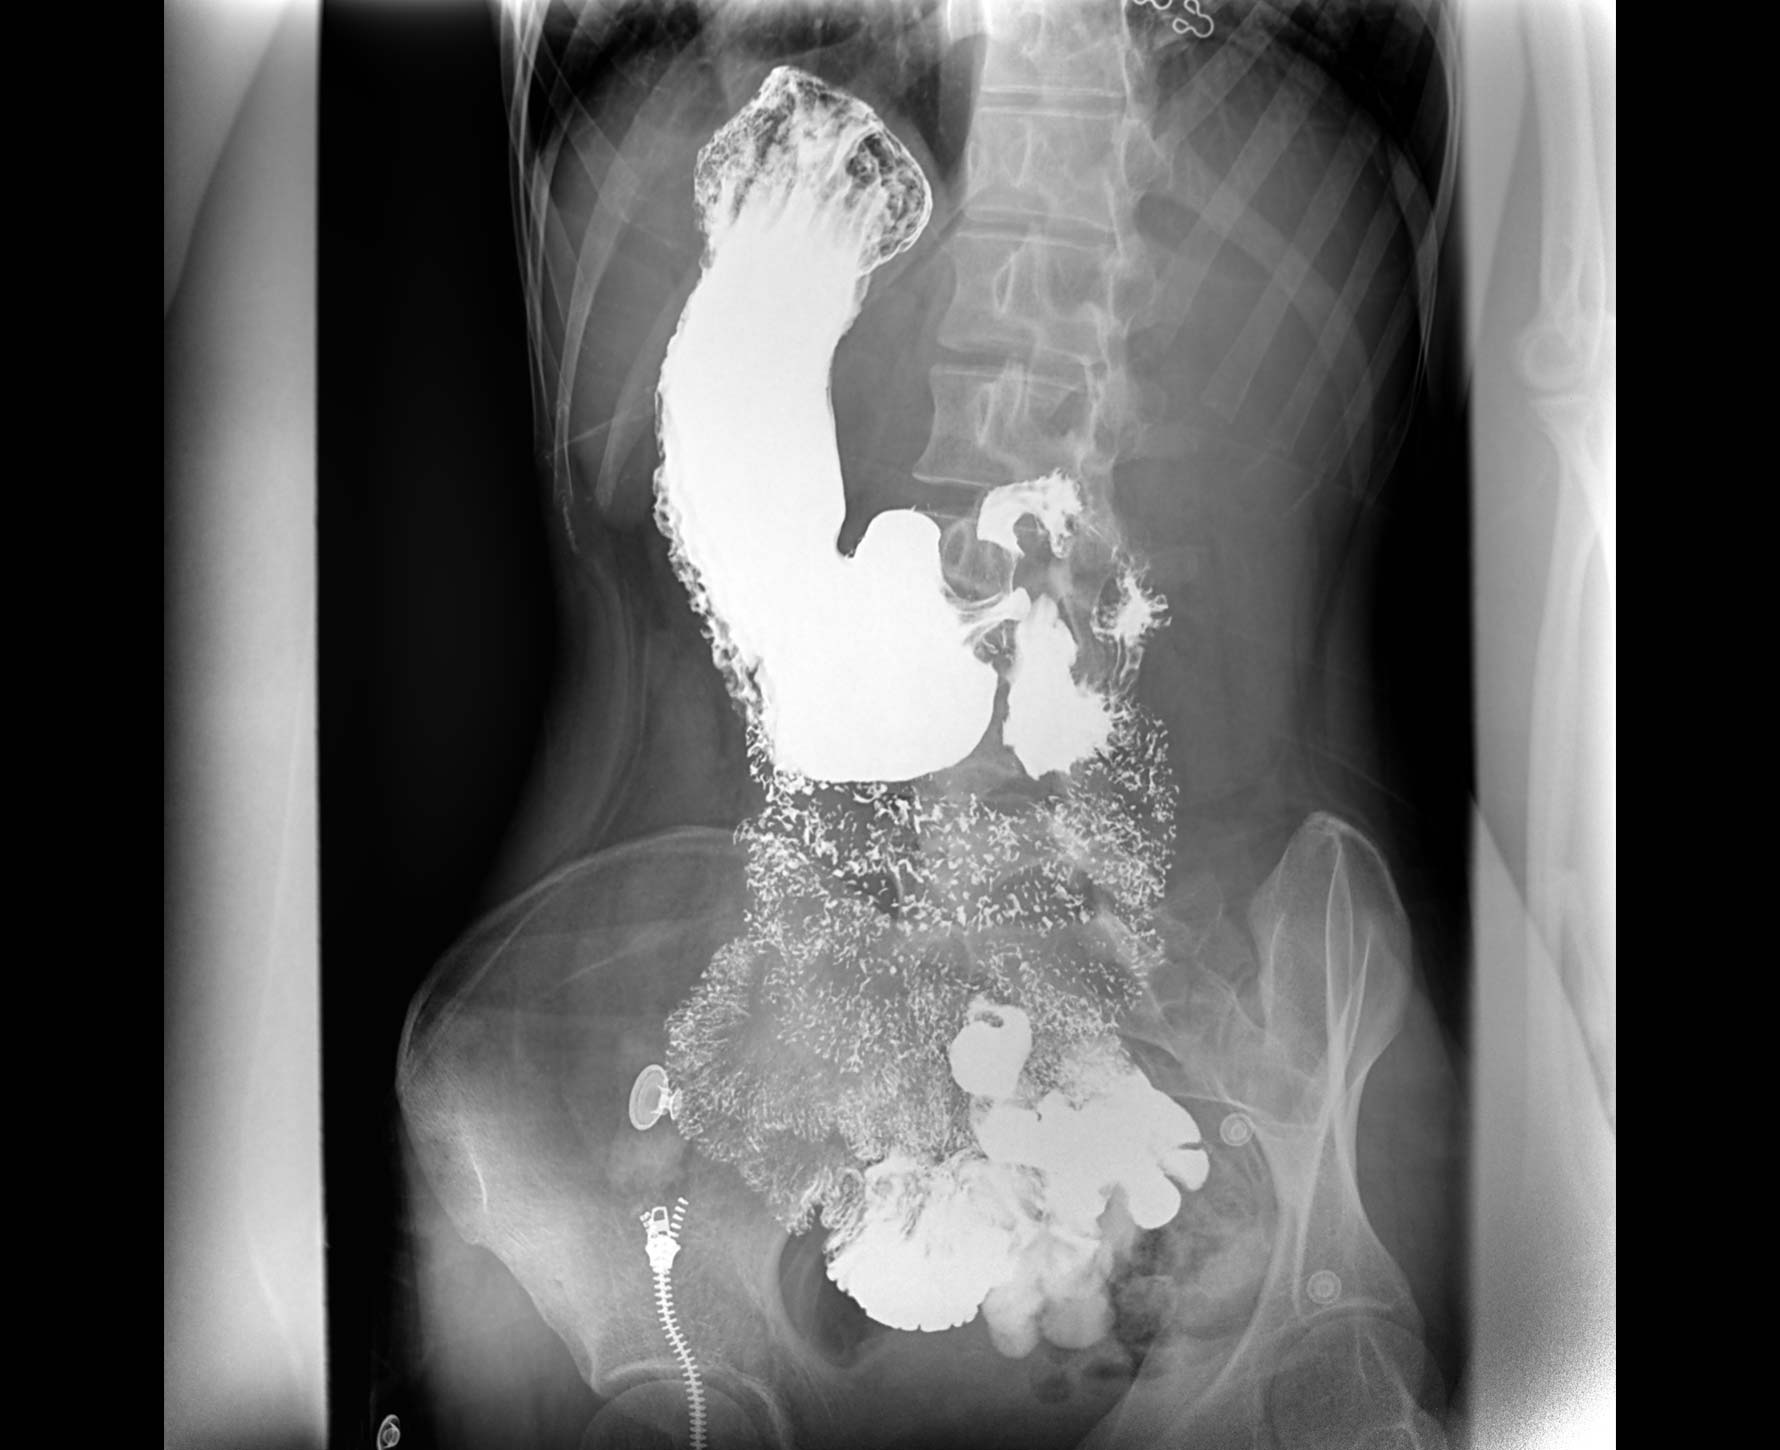

• 造影

适用于各种普通

及特殊胃肠造影检查

• 特有视频保存与回放功能

对胃肠造影检查影像实时保存,多次回放以便确定病灶部位,患者确诊好帮手,减少漏诊。

临床图像